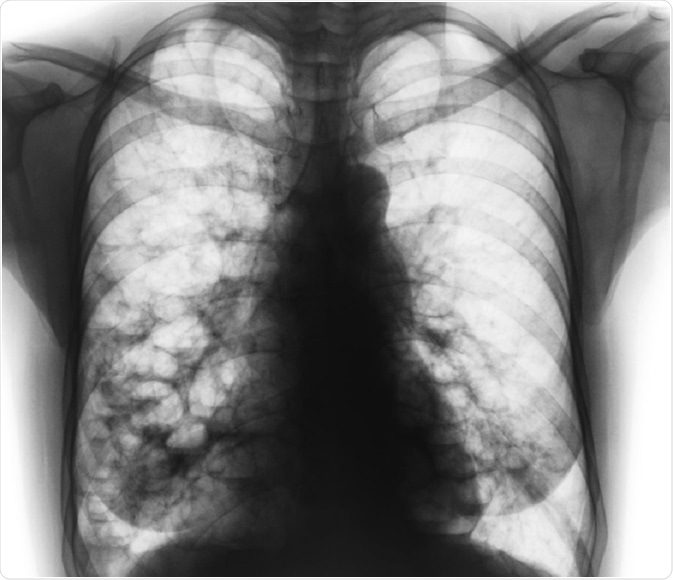

X-ray of lungs that have been damaged by bronchiectasis - photo by Puwadol JaturawutthichaiPuwadol Jaturawutthichai | Shutterstock